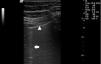

En la EPI se produce disminución de la impedancia acústica entre el aire pulmonar y los tejidos blandos de la pared torácica, porque parte del espacio inicialmente ocupado por el volumen de aire es sustituido por infiltración de células inflamatorias o tejido conectivo, provocando la aparición de alteraciones en la línea pleural y artefactos verticales llamados «líneas B». Las líneas B son indicativas de aumento de la densidad pulmonar subpleural antes de la consolidación y pueden estar causadas por la existencia, aunque no exclusivamente, de enfermedad intersticial25. La línea pleural se vuelve irregular y engrosada y puede aparecer borrosa y fragmentada. Las líneas B se muestran como artefactos verticales en forma de rayo hiperecoico que surgen de la línea pleural y se extienden hasta el final de la pantalla sin desvanecerse, borran las líneas A y se mueven sincrónicamente con el deslizamiento pleural. La presencia de múltiples líneas B es el signo ecográfico que define al «síndrome intersticial»26. En la figura 2 se muestra la TACAR de un paciente con AR y EPI; en la figura 3, los hallazgos de ultrasonido.

Ultrasonido pulmonar realizado a la misma paciente de la figura 2 con equipo GE Logiq 3, con transductor lineal multifrecuencia de 10-14MHz, con la paciente en posición sentada y transductor en orientación longitudinal. La flecha señala una línea B. El triángulo señala la línea pleural, que se observa de aspecto irregular. Nótese la ausencia de líneas A.